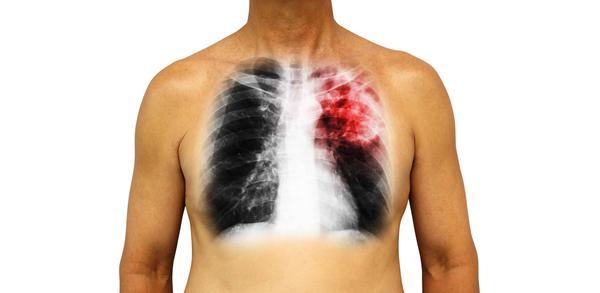

让人担忧的是,肺癌病发率不仅相当高,死亡率也不容忽视。而肺癌高死亡率背后的原因,就与肺癌早期发现困难有直接关系。

就临床掌握的资料来看,肺癌原位癌时期症状多不典型,就算是逐渐有症状显现,也容易让患者认为仅仅只是普通的呼吸道疾病,继而忽视了筛查。

如果男性近期出现了以上几个症状,特别是频繁咳嗽、用药后无缓解,且自己有多年的吸烟史或肺癌家族史,这很可能是肺部已经发生病变的信号,患者需要及时就医进行相关的肺部健康筛查,比如低剂量螺旋CT就是临床常用到的筛查办法之一。